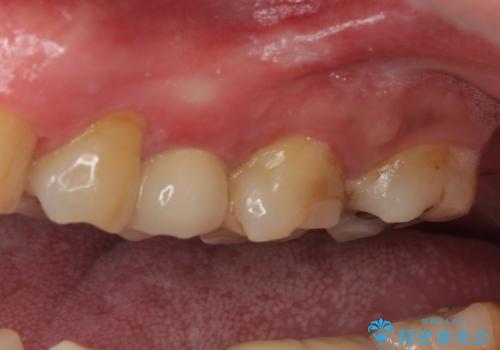

- 奥歯の詰め物が外れてしまったとのことで来院された患者様です。

レントゲン写真より、既に根管治療がされている歯であり、根尖部に骨透過像が認められました。

特に症状はありませんでしたが、根管治療を希望されたため、まずは根管治療を行うこととしました。

根管治療の際に、咬み合う上顎の銀歯が内側に入り込んでいることも気になるとのことであったため、部分矯正を行い、その後上下を同時に補綴治療することとしました。